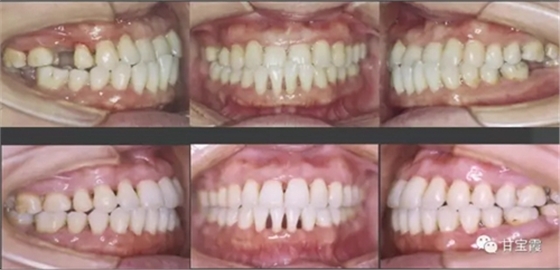

經(jīng)過一年多的正畸治療,關(guān)閉了所有的缺牙間隙,也不用再鑲牙了。

上圖為矯正前后的對(duì)比

其實(shí)她可以選擇種三顆牙,也可以選擇做九顆烤瓷牙,但是她最終還是選擇了用正畸的方法關(guān)閉間隙,這是一個(gè)明智的選擇。同時(shí)還解決了前牙的反頜達(dá)到了美觀的效果。